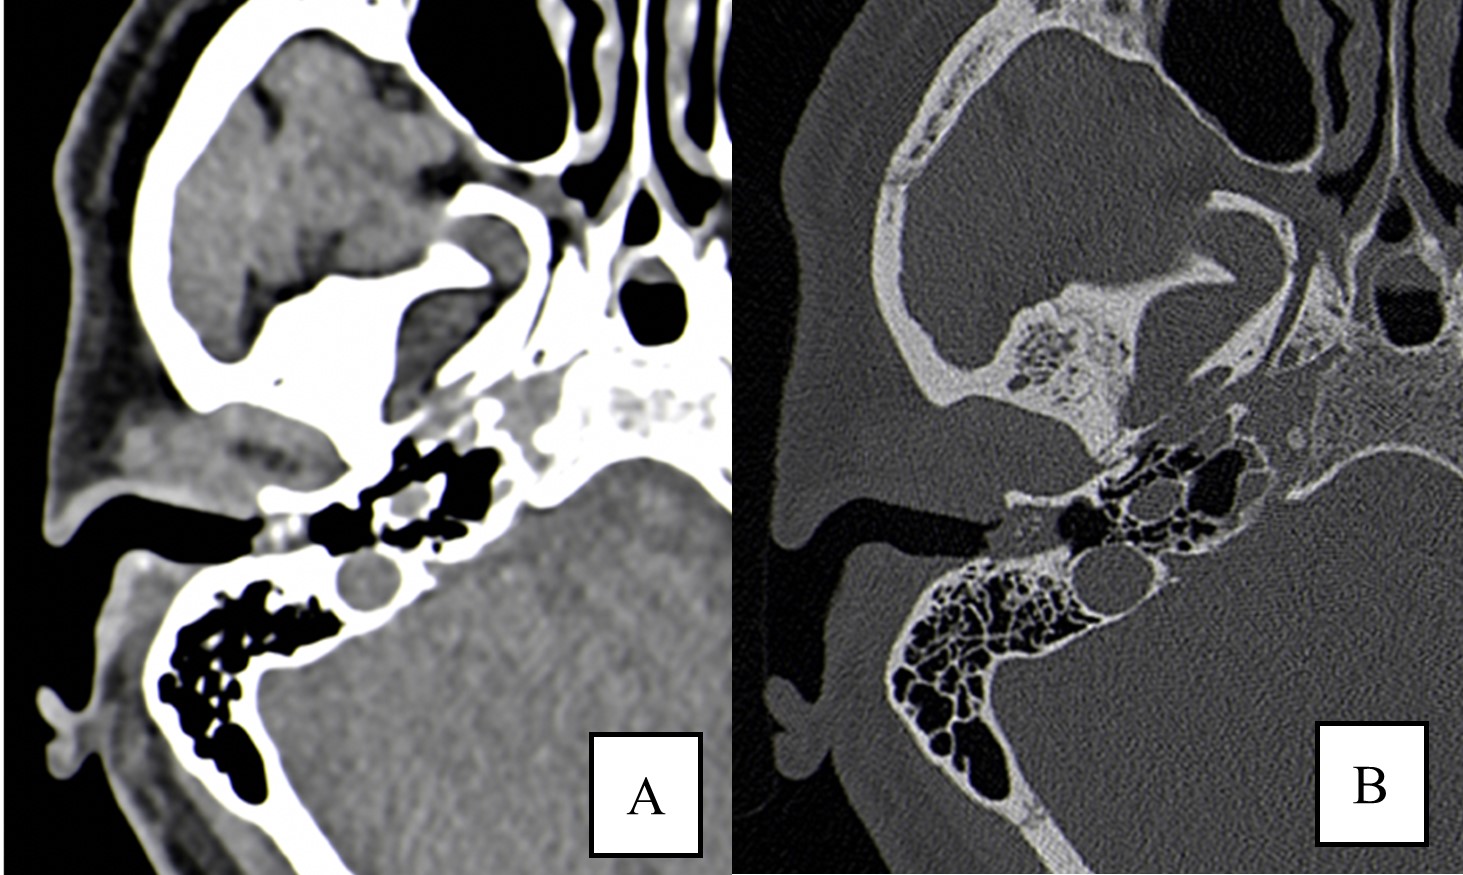

A plain high-resolution temporal bone computed tomography (CT) scan was obtained. A unilateral soft tissue attenuating lesion was present in the posterior-inferior aspect of the right external auditory canal (EAC). Using the bone window setting, it was possible to visualise an area of focal bone erosion of the EAC associated with small bone flecks sequestered within the mass. It is important to note the facial nerve canal and mastoid cells were preserved.

The patient was successfully submitted to a canaloplasty, removing the lesion.(Fig. 1)

Figure 1: (A) High-resolution CT of temporal bone in axial section depicts a lesion of the right EAC on the soft tissue window setting. (B) High-resolution CT of temporal bone in axial section depicts a lesion of the right EAC on a narrowed window width setting. There is erosion of posterior wall and bony sequestrum within the lesion.

EAC cholesteatoma presents on CT as a sharply marginated expansile soft tissue attenuating lesion with bone erosions and small bone flecks within the lesion. These bone flecks are better visualized in narrow window width settings (Fig. 2).3

In this case, the middle ear cavity and the facial nerve canal are uninvolved (3mm distance) and is classified as Stage I according to the CT classification system of Shin et al. (stage I - cholesteatoma of the EAC only; stage II: invasion of the tympanic membrane and the middle ear; stage III: involvement of the mastoid air cells; stage IV: lesions beyond the temporal bone).3

The management of the EAC cholesteatoma depends on the extent of the lesion, which should be assessed by CT. Canaloplasty is indicated for stage I lesions and it was performed in our case. Advanced stages may require a more radical approach with mastoidectomy or petrosectomy (Fig. 3).3